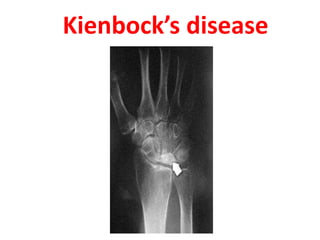

Kienbock’s disease